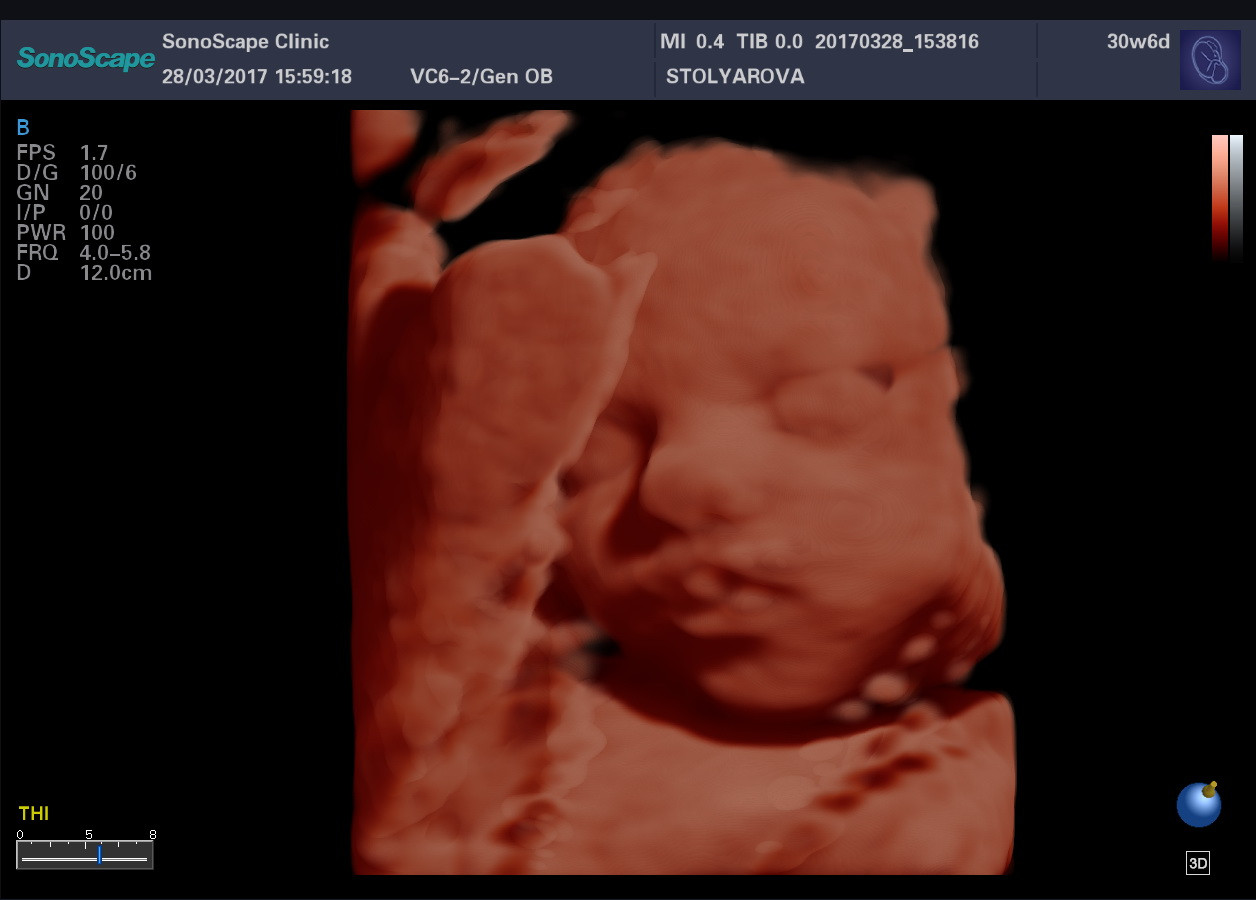

- FreeHand 3D – режим поверхностной трехмерной реконструкции

- 4D – режим трехмерной реконструкции в реальном времени

- Расчеты для акушерства, гинекологии, ангиологии, урологии, ортопедии, поверхностных, абдоминальных органов, кардиологии, головного мозга и сердца плода (в том числе STIC), вывода кривых роста плода, автоматический анализ толщины комплекса интима-медиа